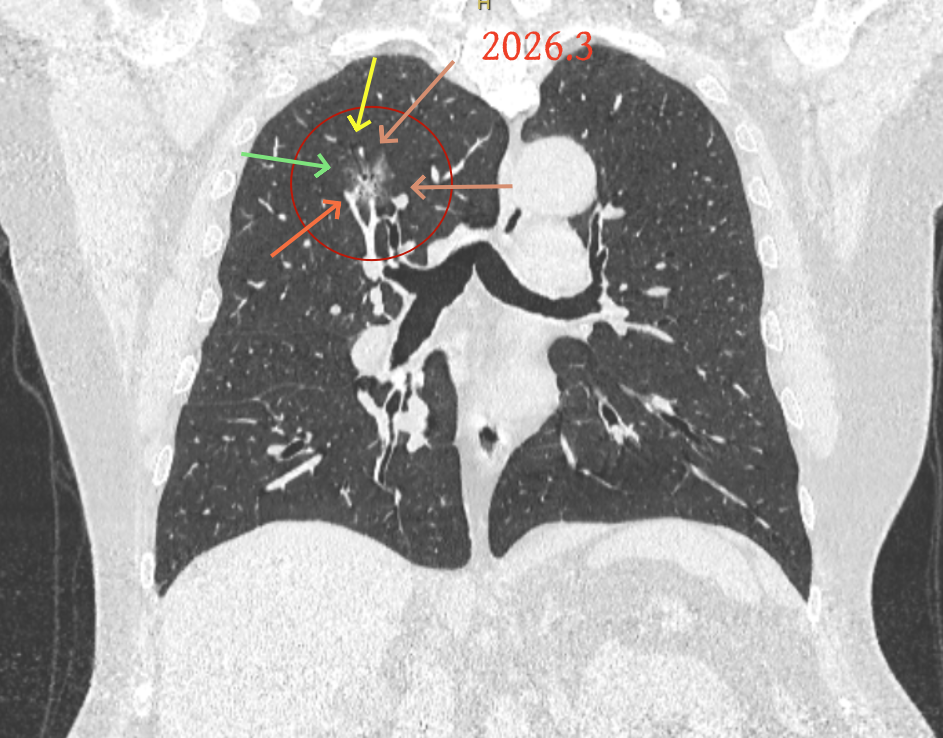

但病灶B却显然进展!变成以实性成分为主的了!

两处均有进展,混合密度这处更显著些。那要考虑手术了的。之前也有碰到较短时间内进展是伴炎症或纤维增生的,但我们不能赌。建议手术为宜。意见供参考!

再看病灶B的2026年3月细节影像特征:

边缘位置也是较淡的磨玻璃成分。

上图是混合密度,轮廓较清,瘤肺边界欠清晰。

病灶A以及他处磨玻璃结节其实进展都是不明显的,略与2022年比,病灶A稍显明显点。病灶B开始时极淡,之前进展虽有但也甚微,直到2025年9月仍是磨玻璃成分为主,只是点状少许密度稍高成分。但在最近半年内却显然进展!若从影像上判断,基本上就得是浸润性腺癌了。那有几点:一是必不能再随访;二是大小来看仍是1A期;三是从快速进展来说,可能含有部分高危亚型,比如微乳头或实体型等;四是他处的磨玻璃结节以及病灶A显然不能用病灶B的转移来解释,仍考虑是多原发早期肺癌。

结友问能否先穿刺?我是这么考虑的:你这个病灶B一是位置深,且靠近附近的血管,不容易穿刺;二是从影像变化来看,基本上肯定是恶性的,不是100%,也是95%以上的概率。刚才我又在重建看冠状位与矢状位以及各次影像,目前混合密度的其实是后来者居上,原来刚开始是它比旁边的病灶密度淡的,但它的密度不是太纯,前次你自己也说似乎有点状偏实性成分。只是最近这半年进展特别快。这说明它的恶性程度较它边上原来就比较明显的那处恶性程度高,亚型中大概率有低分化的成分。所以从目前的影像来看,要尽快手术,而且切肺叶更为稳妥些。

这是较为少见的一个病例,磨玻璃为主,而且一直瘤肺边界欠清晰的病灶何以会在之前三年均极缓慢微小变化的情况下,近半年却快速进展呢?从影像细节上看,我们能否进一步分析哪种纯磨玻璃结节可能会较快进展?结合本例,我个人的考虑是:1、病灶整体显得是磨玻璃密度,但灶内并不均匀,就如磨玻璃密度中混入细沙状;2、整体轮廓虽然较清但瘤肺边界相对来说却并不太清晰;3、邻近有血管紧挨,而且与病灶这间缺乏间隙;4、病灶密度不高,没有明显实性成分,却有灶内有细支气管通气征,说明肿瘤成分具有收缩力,却与纯磨的收缩不匹配(纯磨一般不太会有明显收缩力)。如果有上面这些特征可能要提高警惕,一是适当较短的随访间隔,二是影像细节变化要更加注意,开始变化意味着已经进入发展期,而非蛰伏期。当然是否在2025年9月时定得手术了?如果是孤立性的病灶B,且位置位于能简单楔形切除的位置,那是可以考虑的。但位置深、两肺多发,切除范围不小,再今年据肺癌诊疗指南中说的混合磨玻璃结节实性成分不足25%是非侵袭性病变,且几乎不会转移,那么按原则仍再随访显然是可以的。本例的随访变化再次表明磨玻璃密度肺癌的诊疗个体化之路仍是很漫长的,按指南原则的随访或诊疗显然不足以覆盖所有病例,总结与经验积累永远在路上。